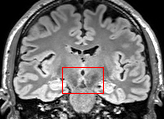

To test the impact of the iterative refinement on YODA’s translation quality, we compared regression and diffusion sampling on the RS data and present additional generation examples in Fig. 6. We observe that diffusion sampling visually resembles the appearance of the acquired images. Regression sampling preserves key anatomical features – the GM/WM boundary, WMHs (Fig. 4), the outline of the pallidum (Fig. 6) – but omits many high-frequency features. To investigate whether iterative refinement during diffusion sampling adds relevant and systematic medical information or only imitates acquisition noise, we performed ExpA sampling, i.e. averaging the output of several ( or ) diffusion trajectories. We observed a gradual loss of high-frequency details when increasing the (see also the supplementary video), indicating that the effect of the iterative refinement is non-systematic. For , the images are visually almost indistinguishable from the initial regression solution (see the supplementary video, and Fig.4 and 6). We directly compared the synthesis results of ExpA () and regression sampling quantitatively and found the differences to be minimal (SSIM: 99.73%, PSNR: 45.30 dB), i.e. diffusion sampling approaches the initial regression solution for a high . The quantitative analysis of the image quality (Tab. 1) showed that diffusion sampling impairs the assessed SSIM and PSNR in comparison to regression sampling for both the in- and external test sets, which we attribute to noise generation (Sec. 3.1). In turn, ExpA averages improved both metrics and, for , performed mostly on par with the regression solution in both test sets in terms of SSIM, while the PSNR in the RS was slightly increased (Tab. 1). However, we observed that ExpA sampling YODA improves the replication of systematic 3D low-frequency image intensity drifts (bias fields) due to the 3D synchronization in 2.5D diffusion sampling. Yet, this apparent advantage did not generalize to the external MBB dataset, as bias fields are MR protocol-specific.

We evaluated the impact of the proposed sampling methods on the performance of the independent, externally trained SHIVA-WMH tool as compared to manual reference labels (Tab. 1). Smoother images (higher or from regression sampling) yielded improved performance over those from diffusion sampling.

To assess the suitability of YODA-generated images for WMH detection independent of segmentation tools, we also calculated the CNR (15) of WMHs. This confirmed that the contrast of WMHs is preserved in the regression images, whereas we noted slightly reduced WMH contrast for diffusion and ExpA-sampled images (Tab. 1).

On the RS data (Tab. 1), regression sampling of YODA significantly outperformed all competing methods both w.r.t. the image quality and – except the ALVR for MADM – downstream WMH segmentation, whereas the DB of Choo et al. [31] achieved an higher WMH CNR.

When analyzing the RS synthesis results (Fig. 4), we noted that most reference methods strive to imitate realistic images, but several artifacts can be observed such as hallucinated WMHs (SynDiff) and salt-and-pepper noise (SynDiff, I2I-Mamba, ResViT).